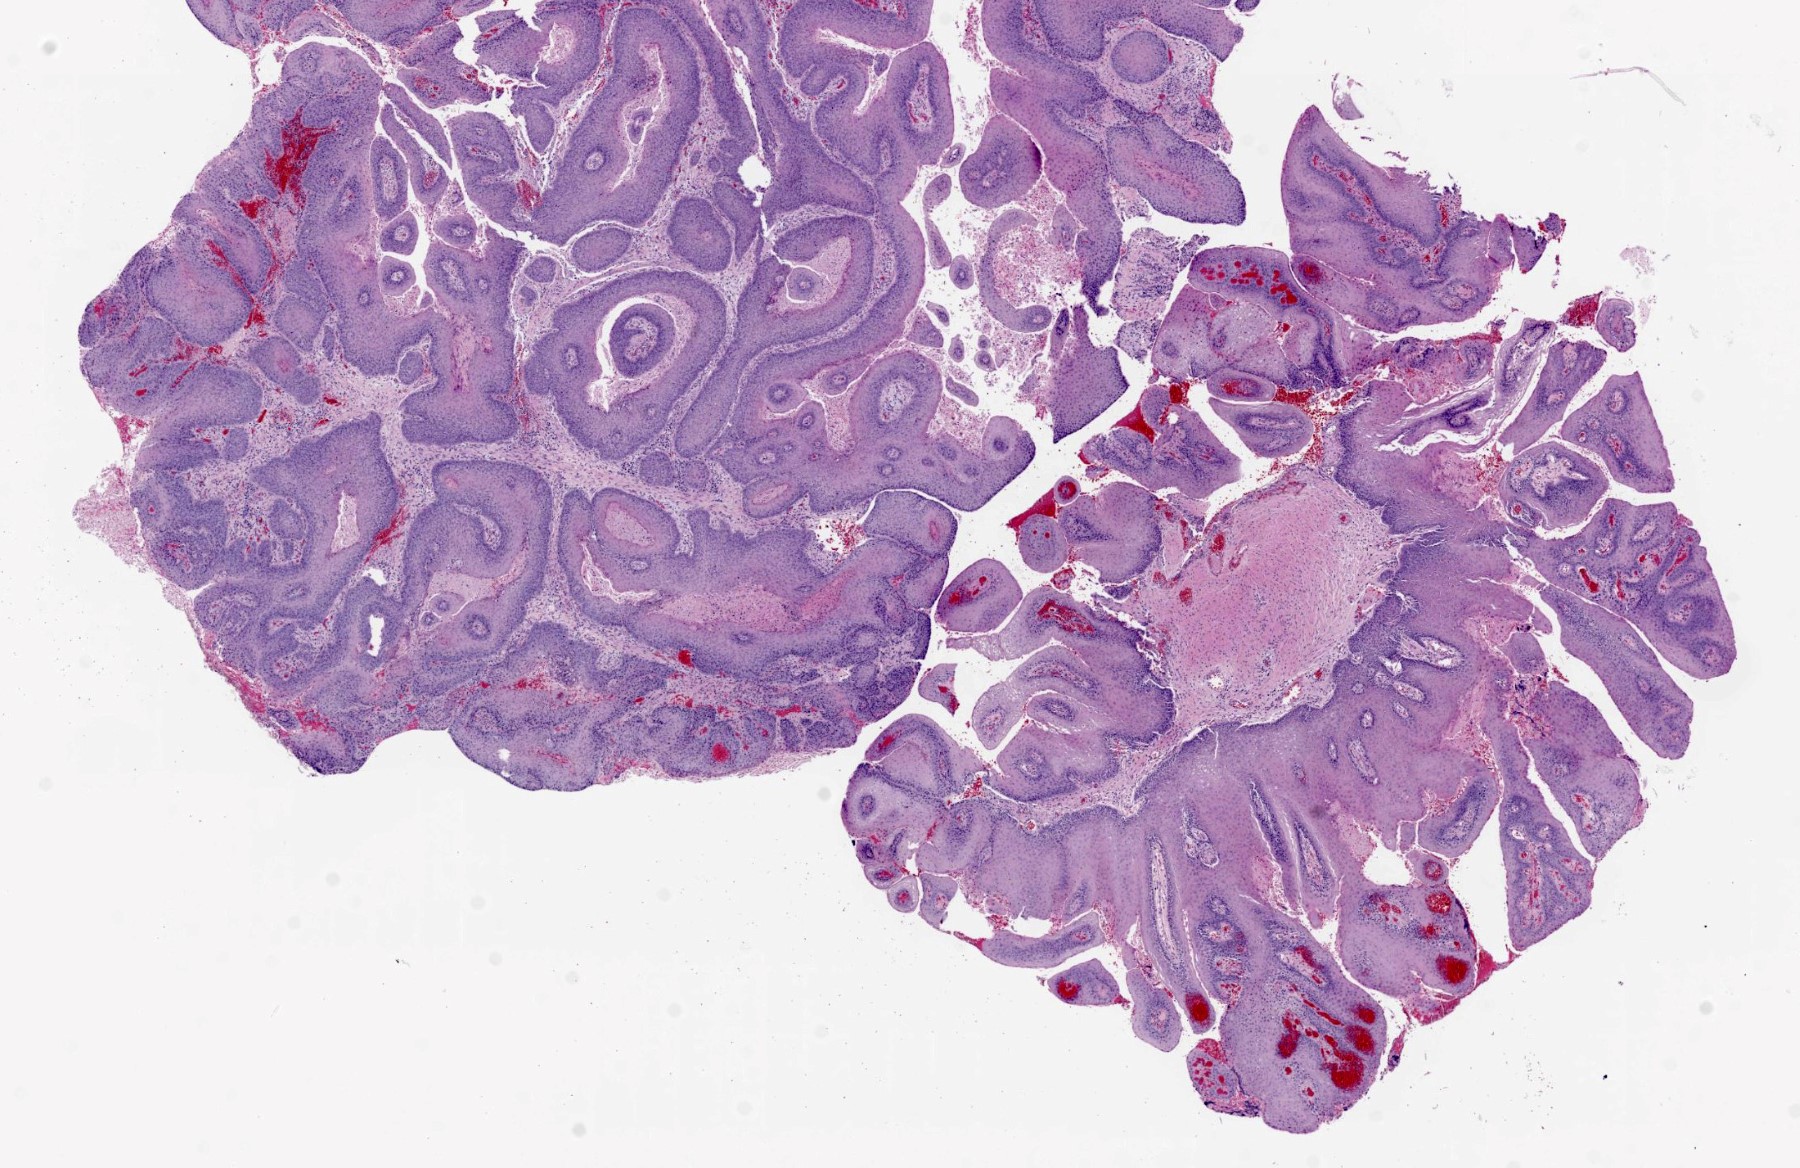

Microscopic (histologic) description

- Finger-like projections or multiple fronds with a central fibrovascular core, covered by benign hyperplastic stratified squamous epithelium

- Basal and parabasal hyperplasia

- Increased mitotic figures in the basal and parabasal layers

- Koilocytic changes in upper layer: may be pronounced or subtle

- Surface keratinization: absent to minimal

- Malignant transformation is characterized by aberrant (paradoxical) keratinization, marked cytological atypia, focal necrosis, increased mitoses and atypical mitoses not limited to the basal and parabasal layers, as well as invasive growth pattern (Respir Med 2017;126:116)

Microscopic (histologic) images